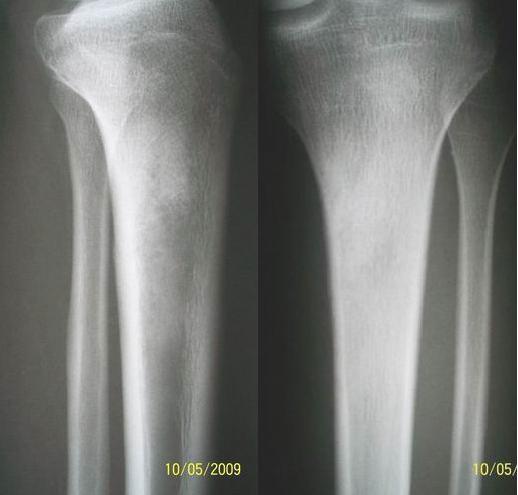

男,16岁,胫骨近端疼痛月余,压痛明显,轻度肿胀,无发红,无其他临床征象。图片如下

髓腔密度增高,不除外骨纤.

髓腔密度增高,不除外骨纤

时间短,肿胀压痛,不排外骨髓炎早期改变

此例平片的价值要大于ct,平片的征象本来很明确,但是ct并没有表现什么,这是本病例的特殊性,一周后公布结果

病例结果:骨肉瘤